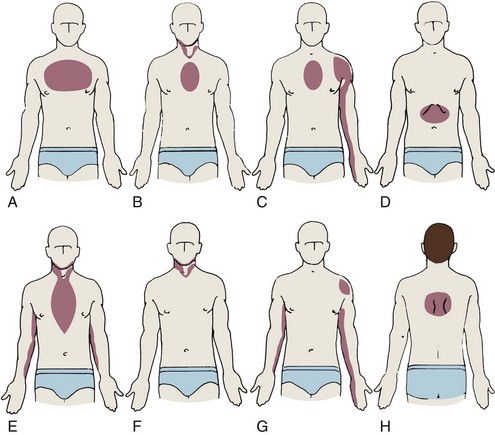

На изображении показаны типичные зоны распространения боли при сердечно-сосудистых заболеваниях. Боль может ощущаться не только за грудиной, но и распространяться в левое плечо, руку, шею, межлопаточную область или верхнюю часть живота. Именно такая иррадиация боли часто становится причиной того, что пациенты путают боль в грудном отделе позвоночника с сердечной болью.

Важно учитывать, что при мышечно-скелетных причинах боль в грудном отделе позвоночника чаще локализована между лопатками или вдоль позвоночника и изменяется при движении, тогда как боль сердечного происхождения обычно сопровождается чувством давления в грудной клетке и не зависит от положения тела.